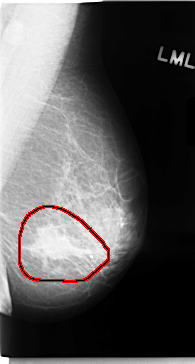

C_0050_1.LEFT_MLO

FILE: C_0050_1.LEFT_MLO.OVERLAY

TOTAL_ABNORMALITIES 1

ABNORMALITY 1

LESION_TYPE MASS SHAPE IRREGULAR MARGINS SPICULATED

ASSESSMENT 5

SUBTLETY 5

PATHOLOGY MALIGNANT

TOTAL_OUTLINES 1

BOUNDARY